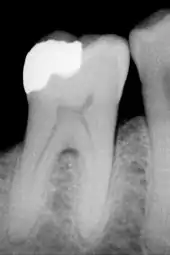

- La technique indirecte consiste à prendre l'empreinte de la cavité que l'on veut obturer, le prothésiste fabrique ensuite la pièce juste manquante. Les matériaux pouvant être utilisés sont : les métaux et alliages métalliques (or, nickel-chrome, chrome-cobalt), la résine cuite, la céramique (ou porcelaine). La pièce issue de cette technique s'appelle un inlay. Quand la cavité est très grosse et que des parties entières de dents sont à reconstruire, on les appelle onlay. Cette technique a comme avantage d'être très pérenne, très satisfaisante esthétiquement (sauf quand le matériau utilisé est métallique), mais extrêmement onéreuse (de 10 à 20 fois le prix d'une restauration par technique directe).

En méthode indirecte par inlay ou onlay

Les méthodes indirectes d’inlay (« incrustation ») ou d’onlay (« recouvrement ») se distinguent des techniques à l'amalgame (nécessitant une cavité en contre-dépouille pour être rétentive) par la cavité de dépouille[3] (cavité permettant l'insertion d'une pièce unique et solide, donc ayant une ouverture plus large que sa base) qui leur est nécessaire. De ce fait, l’inlay ou l’onlay nécessite un collage, au même titre que les composites. Dans le cas d'une dépose de plombage et de son remplacement par un inlay, il est nécessaire de retailler au moyen d'une fraise dentaire la cavité de la dent où se trouvait la carie. Cette opération se fait sous anesthésie locale préalable. L’inlay adhère toujours à l'émail de la dent.